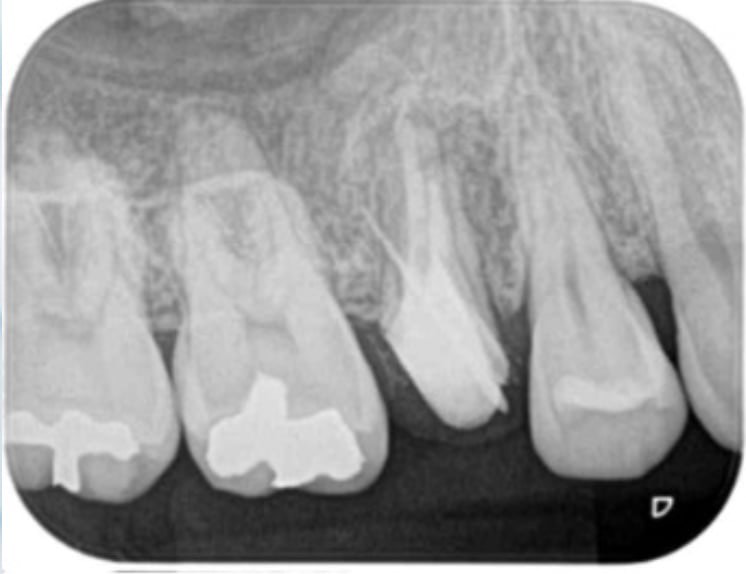

A comparison of survival of teeth following endodontic treatment performed by general dentists or by specialists

Bradley S Alley, DMD, G Gray Kitchens, DMD, Larry W Alley, DMD, Paul D Eleazer, DDS, MS

Oral Surgery,Oral Medicine,Oral Pathology,Oral Radiology,and Endodontology Volume 98, Issue 1, July 2004, Pages 115-118